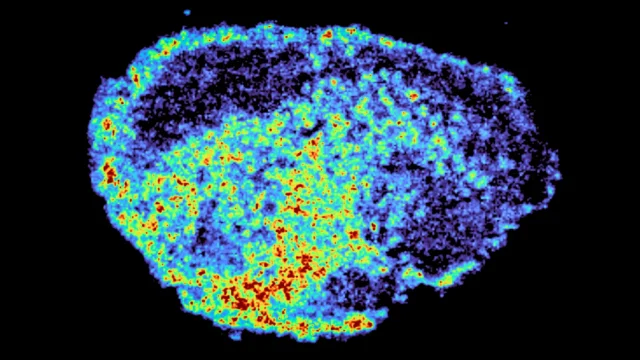

A equipe de pesquisa usou tecnologia de espectrometria de massa para criar mapas detalhados mostrando exatamente onde a droga se acumula. Eles combinaram isso com a transcriptômica espacial, o que lhes permitiu examinar a atividade genética em regiões com níveis altos e baixos de drogas na mesma amostra. Os resultados mostraram diferenças significativas na distribuição de medicamentos dentro de tumores individuais e entre pacientes, mesmo quando se utilizou a mesma dose.

“Um aspecto novo deste estudo é o uso de imagens de espectrometria de massa para medir e visualizar diretamente a captação de drogas no tecido tumoral do paciente. Através do mapeamento espacial de moléculas de drogas, podemos usar a transcriptômica espacial para identificar regiões de níveis altos e baixos de drogas e comparar a expressão genética nas mesmas seções de tecido”, disse a autora sênior Zoe Hall, PhD, professora associada do Departamento de Metabolismo, Digestão e Reprodução do Imperial College London.